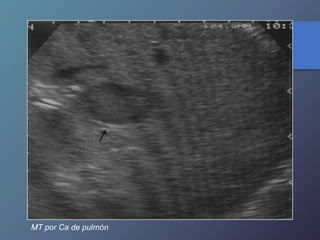

MT hipoecoicas:

• Son hipovasculares.

• Origen CA de mamas, pulmón, páncreas y esófago.

MT por Ca de pulmón

MT por Cade pulmón